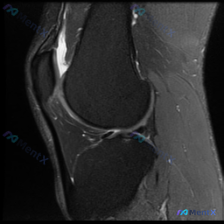

看到这个膝关节读片的病例,整理了完整信息和分析思路分享给大家。 病例基本信息 核心问题:临床怀疑膝关节存在软骨异常,提供单张膝关节矢状位MRI,请分析图像中的明显发现。 影像基础信息 这是一张清晰度良好的膝关节矢状位PD/T2加权MRI,左侧为前(髌骨侧),右侧为后,上方为股骨远端,下方为胫骨近端,...